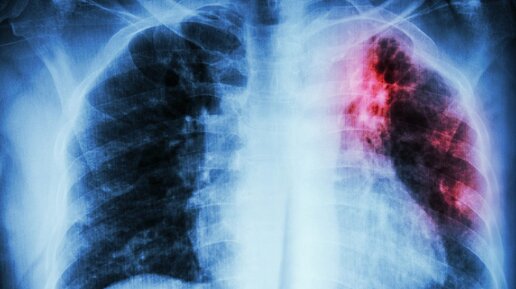

Одной из самых распространенных инфекций в современном нам мире является туберкулез. Возбудителем этой патологии является палочка Коха. Ее опасность заключается в том, что заразиться можно воздушно-капельным путем, то есть при обычном контакте с человеком. Больной человек особенно опасен для других, если патология протекает в открытой форме, так как вместе с его мокротой выделяется большое количество микобактерий. Особенно опасна открытая форма туберкулеза для людей с низким иммунитетом. Туберкулез, при котором происходит постоянное выделение микобактерий во внешнюю среду, называется открытый...